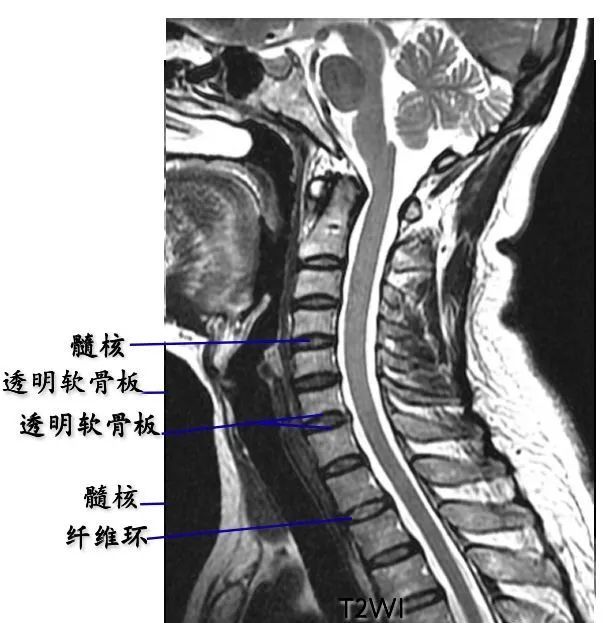

椎间盘:呈软组织密度影,CT值为70±5HU,不能区分髓核和纤维环

髓核:T2WI上呈较高信号

纤维环:T1WI和T2WI上均显示为低信号

sharpey纤维:T1WI和T2WI上均显示为低信号

透明软骨板:T1WI和T2WI上均显示为低信号